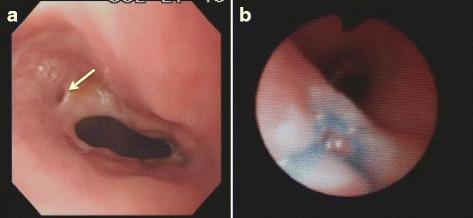

Recurrent tracheoesophageal fistula (TEF) is still difficult to diagnose and repair. In almost all cases, recurrence appears relatively soon after the primary surgery. We herein describe a case of recurrent TEF that appeared 10 years after the primary repair. At 2 years of age, the patient suffered from mental retardation due to encephalitis and developed a hiatus hernia with gastro-esophageal reflux. He underwent the repair of a hiatus hernia and fundoplication at 3 years of age. However, the hiatus hernia recurred 6 months after the operation. The patient suffered from recurrent pneumonia for 6 years after the appearance of the recurrent hiatus hernia. At 9 years of age, he was hospitalized frequently due to recurrent severe pneumonia. After admission at 9 years of age, an endoscopic study under general anesthesia was performed and revealed subglottic stenosis and a dilated esophagus with a recurrent hiatus hernia. Tracheotomy or laryngotracheal separation was first planned in order to improve his upper airway and facilitate the safer repair of the recurrent hiatus hernia. After laryngotracheal separation, the patient still suffered from severe pneumonia. In addition, a small volume of nutritional supplement was aspirated from the tracheostomy. Thus, recurrent TEF was suspected. Tests using dye under both esophagoscopy and bronchoscopy confirmed recurrent TEF. The fistula recurred in the cervical area because of the elevation of the esophagus due to the recurrent hiatus hernia. The fistula was surgically closed, with a sternothyroid muscle flap to prevent re-recurrence. At 4 months after this operation, the recurrent hiatus hernia was repaired. Thereafter, the patient's respiratory symptoms showed a dramatic improvement. The patient is now doing well and free from further recurrences of TEF and hiatus hernia at 2 years after the final operation.

复发性气管食管瘘(TEF)的诊断和修复仍然困难。几乎在所有病例中,复发都出现在初次手术后相对较短的时间内。我们在此描述一例初次修复术后10年出现的复发性TEF病例。患者2岁时因脑炎导致智力发育迟缓,并出现伴有胃食管反流的食管裂孔疝。他在3岁时接受了食管裂孔疝修补术和胃底折叠术。然而,术后6个月食管裂孔疝复发。复发性食管裂孔疝出现后,患者反复发生肺炎6年。9岁时,他因反复严重肺炎频繁住院。9岁入院后,在全身麻醉下进行了内镜检查,发现声门下狭窄和扩张的食管伴有复发性食管裂孔疝。最初计划进行气管切开术或喉气管分离术,以改善其上呼吸道并便于更安全地修复复发性食管裂孔疝。喉气管分离术后,患者仍患有严重肺炎。此外,从气管造口吸出少量营养补充剂。因此,怀疑有复发性TEF。在食管镜检查和支气管镜检查下使用染料进行的测试证实了复发性TEF。由于复发性食管裂孔疝导致食管抬高,瘘管在颈部区域复发。通过胸骨甲状肌瓣手术关闭瘘管,以防止再次复发。此次手术后4个月,修复了复发性食管裂孔疝。此后,患者的呼吸道症状有了显著改善。在最后一次手术后2年,患者目前情况良好,未再出现TEF和食管裂孔疝的复发。